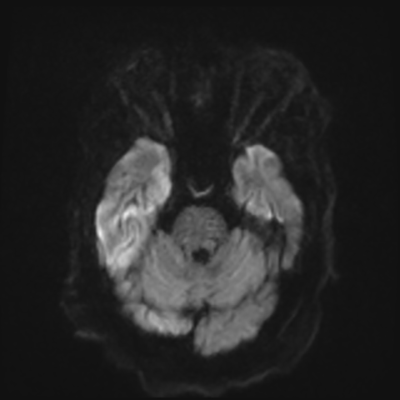

You come back the next day and see how things are going. The patient's electrographic record has shown a moderate encephalopathy (diffuse slowing, disorganization) with frequent right posterior quadrant delta slowing. Based on this result, and an adequately improved clinical examination, you give the okay to proceed with obtaining an MRI of his brain. This is shown below.

MRI brain (DWI)